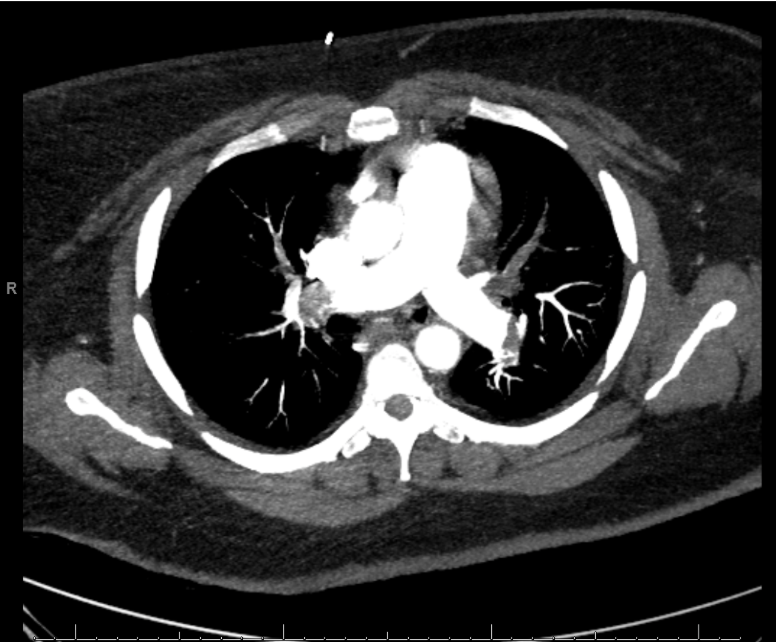

Case Presentation: Cardiopulmonary resuscitation (CPR) is a critical intervention in cardiac arrest management, essential for maintaining circulation and oxygenation to avert irreversible brain damage. This case report highlights the impact of high-quality CPR on neurological outcomes, even after extended resuscitation.A 45-year-old sedentary female with multiple sclerosis (MS) and morbid obesity with a BMI of 53 presented with gastrointestinal and dyspnea symptoms post-immunotherapy. Imaging identified bilateral lower lobe pulmonary embolisms and a saddle embolus with significant thrombus burden and right heart strain. During suction thrombectomy, the patient experienced pulseless electrical activity (PEA) arrest. Manual CPR was immediately initiated, and the patient was intubated 12 minutes later. Due to the patient’s body habitus, robotic compressions could not be performed. Sustained return of spontaneous circulation (ROSC) was achieved after 70 minutes, despite transient ROSC episodes. Throughout the resuscitation, she received 13 doses of epinephrine and 4 doses of sodium bicarbonate. Following the event, the patient required hemodialysis due to renal deterioration but stabilized hemodynamically five days later. She regained cognitive capacity and full motor function within 10 days, leading to discharge after a 28-day hospitalization.